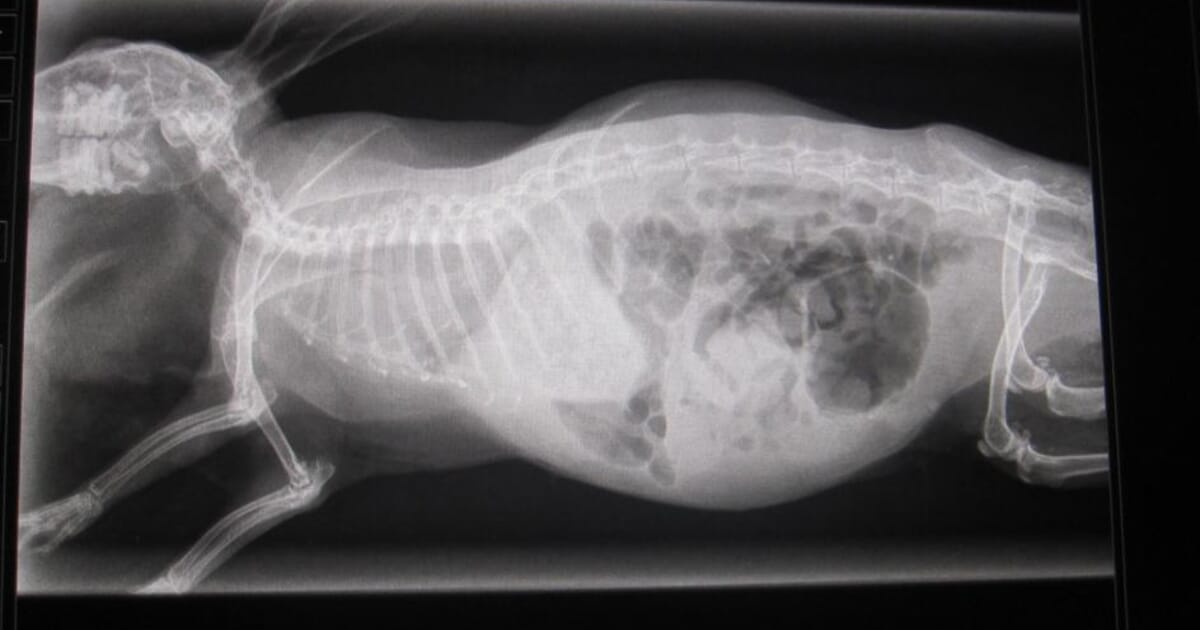

Pregnancy which is important in rabbit production because it is possible to know the number of carried embryos and finally to establish standard data in rabbit production to evaluate the gestational age.